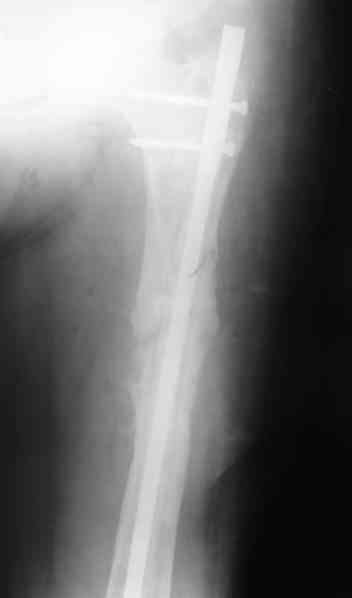

Вчера наш пациент был на контрольном осмотре. Вроде все идет нормально. Рентгенограммы от 25 сентября 2007 г. (прошло 5 месяцев после операции) прилагаю.